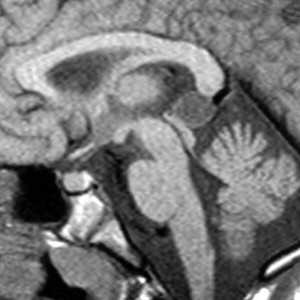

(а) MPT, Т1 -ВИ, сагиттальный срез: у мужчины 25 лет с несвязанными с липомой симптомами определяется гипоталамическая липома, локализованная в сером бугре гипоталамуса (между воронкой и сосцевидными телами).

(б) МРТ, Т1-ВИ, сагиттальный срез: определяется липома ЕЯ крыши среднего мозга, расположенная непосредственно позади нижнего отдела крыши и между нижними холмиками и верхней поверхностью червя мозжечка. Такая локализация липомы встречается очень часто. (а) MPT, Т1 -ВИ, аксиальный срез: в цистерне правого мостомозжечкового угла определяется округлая липома, прилегающая к внутреннему слуховому проходу (ВСП). Липомы не вызывают потерю слуха и не должны подлежать резекции.